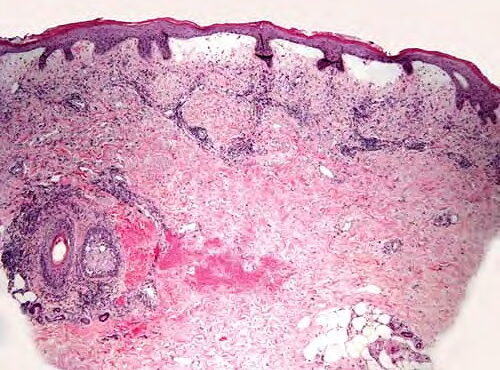

Bullous pemphigoid =الفقاعاني الفقاعي OLYMPUS DIGITAL CAMERA OLYMPUS DIGITAL CAMERA OLYMPUS DIGITAL CAMERA OLYMPUS DIGITAL CAMERA OLYMPUS DIGITAL CAMERA OLYMPUS DIGITAL CAMERA OLYMPUS DIGITAL CAMERA OLYMPUS DIGITAL CAMERA OLYMPUS DIGITAL CAMERA Bullous Pemphigoid First described in 1953 by Lever, bullous pemphigoid affects primarily elderly patients with large tense bullae arising on urticarial erythematous bases or […]